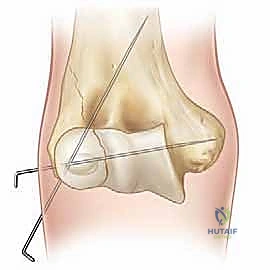

ثانياً: العلاج الجراحي (الرد المفتوح أو المغلق والتثبيت الداخلي)

الجراحة هي المعيار الذهبي والأكثر أماناً لأي كسر متحرك (أكثر من 2 ملم) أو الكسر الذي تعرض للدوران (Jakob Stage 2 & 3). الهدف من الجراحة هو إعادة القطعة المكسورة إلى مكانها بدقة ميكروسكوبية وتثبيتها بقوة لمنع حركة العضلات من إزاحتها مرة أخرى، مما يسمح للعظم بالالتئام السليم.

الخطوات التفصيلية للعملية الجراحية (الرد المفتوح والتثبيت الداخلي - ORIF)

بالنسبة للآباء، تعتبر فكرة خضوع طفلهم لعملية جراحية أمراً مرعباً. لكن فهم الخطوات الدقيقة للعملية يزيل الغموض ويبعث على الطمأنينة. يقوم الأستاذ الدكتور محمد هطيف بإجراء هذه العمليات بمهارة فائقة وتقنيات تحافظ على الأنسجة الرخوة.

1. التخدير والتحضير:

تُجرى العملية تحت التخدير العام لضمان عدم شعور الطفل بأي ألم ولضمان استرخاء العضلات تماماً. يتم تعقيم الذراع بالكامل وتغطيتها بمفارش جراحية معقمة. يتم استخدام جهاز الأشعة السينية المتحرك (C-arm) داخل غرفة العمليات.

2. الشق الجراحي (الوصول الآمن):

يُجري الجراح شقاً جراحياً صغيراً ودقيقاً (غالباً ما يكون تجميلياً) على الجانب الخارجي للكوع. الهدف هو الوصول إلى منطقة الكسر دون إتلاف الأعصاب أو الأوعية الدموية.